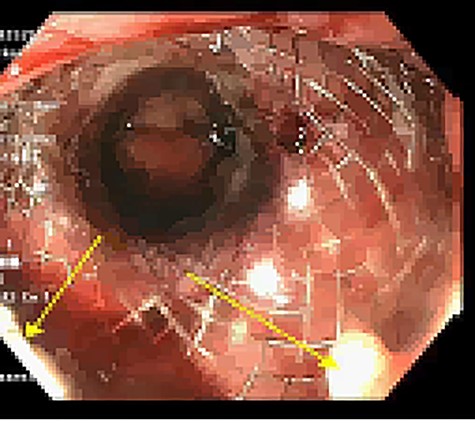

Approximately 2 months into his postoperative course, he returned with symptoms of dysphagia. esophagogastroduodenoscopy (EGD) revealed benign-appearing stenosis at the level of the esophagogastric anastomosis. This was initially dilated with a balloon. However, due to recurrent symptoms, a fully covered SEMS was placed to alleviate stricture (Figs 1, 2). The patient did well for nearly 2 months before returning with recurrent symptoms. A new web was visualized causing complete luminal obstruction (Fig. 3). This was unable to be traversed in antegrade fashion, requiring retrograde access via the jejunostomy utilizing guidewire. A pediatric colonoscope was able to be passed over the guidewire and dilate before subsequent SEMS deployment (Fig. 4). This stent was secured using 2-0 polypropylene suture via Overstitch device (Fig. 5). The initial SEMS was found to have migrated to the mid portion of the gastric conduit. However, due to the small caliber of the proximal stricture and to avoid disrupting newly deployed stent, the initial SEMS was left in place.

Retrograde guidewire, with subsequent pediatric colonoscope and SEMS placement.

Colonoscopic identification of SEMS within the transverse colon.